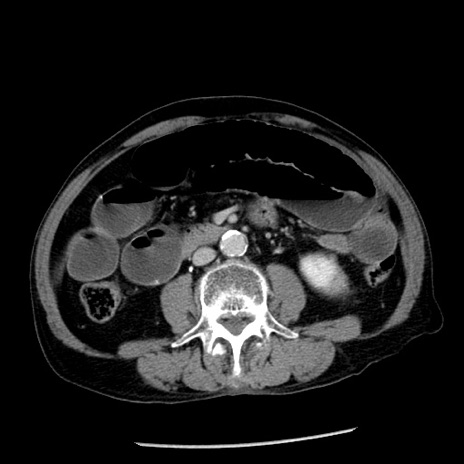

症例26(横断像)

【症例】80歳代男性

【主訴】嘔吐

【現病歴】昨晩2回嘔吐あり、今朝になっても嘔吐あり。来院。

【既往歴】胃潰瘍

【身体所見】意識清明、BT 37.6℃、BP 166/95mmHg、HR 100bpm、SpO2 97%、腹部:平坦・軟、腸蠕動音聴取良好、圧痛なし。

【データ】WBC 21900、CRP 1.46